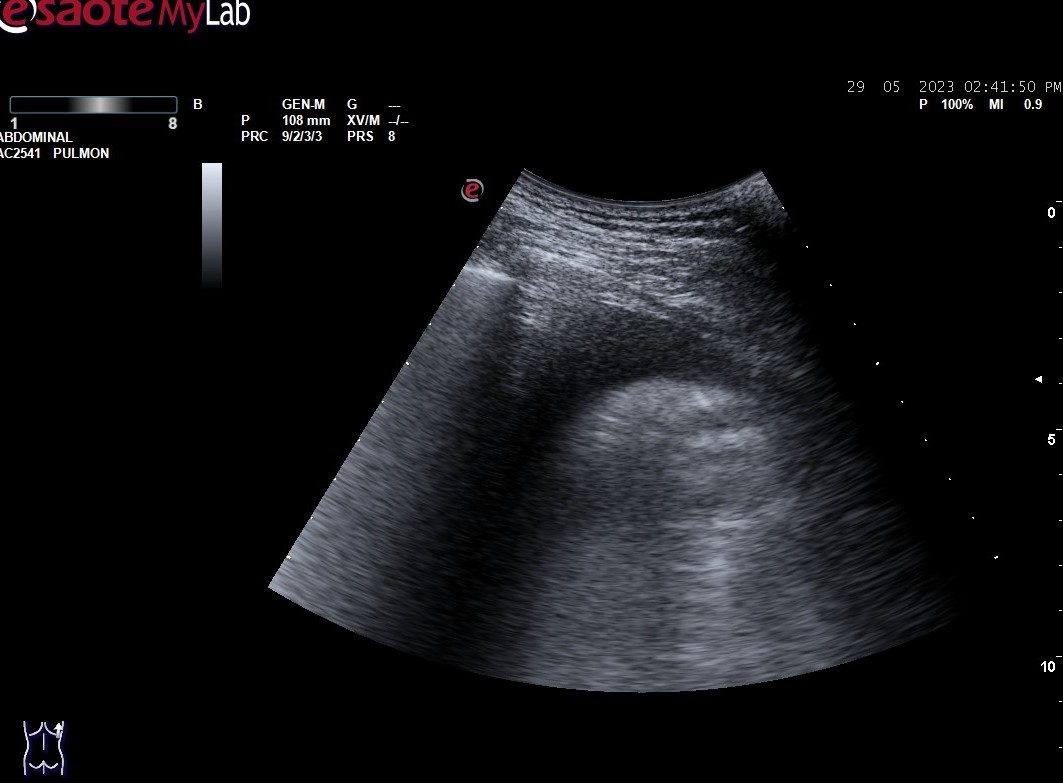

Hallazgos ecográficos: derrame pleural bilateral y abundantes líneas B (más de 3 por espacio intercostal) en ambos 1/3 medios inferiores bilaterales (adjuntamos imágenes).

En la ecografía pulmonar observamos unos patrones ecográficos (normal, deslizamiento pleural, líneas A, líneas B, derrame pleural y consolidación pulmonar). Realizando una serie de preguntas dicotómicas sobre estos patrones ecográficos se establece un algoritmo (protocolo BLUE) que permite establecer con alta sensibilidad y especificidad la causa de la disnea mediante un árbol de decisión.

Aplicando dicho protocolo establecemos un diagnóstico ecográfico de presunción de Edema Agudo de Pulmón/Insuficiencia cardíaca.